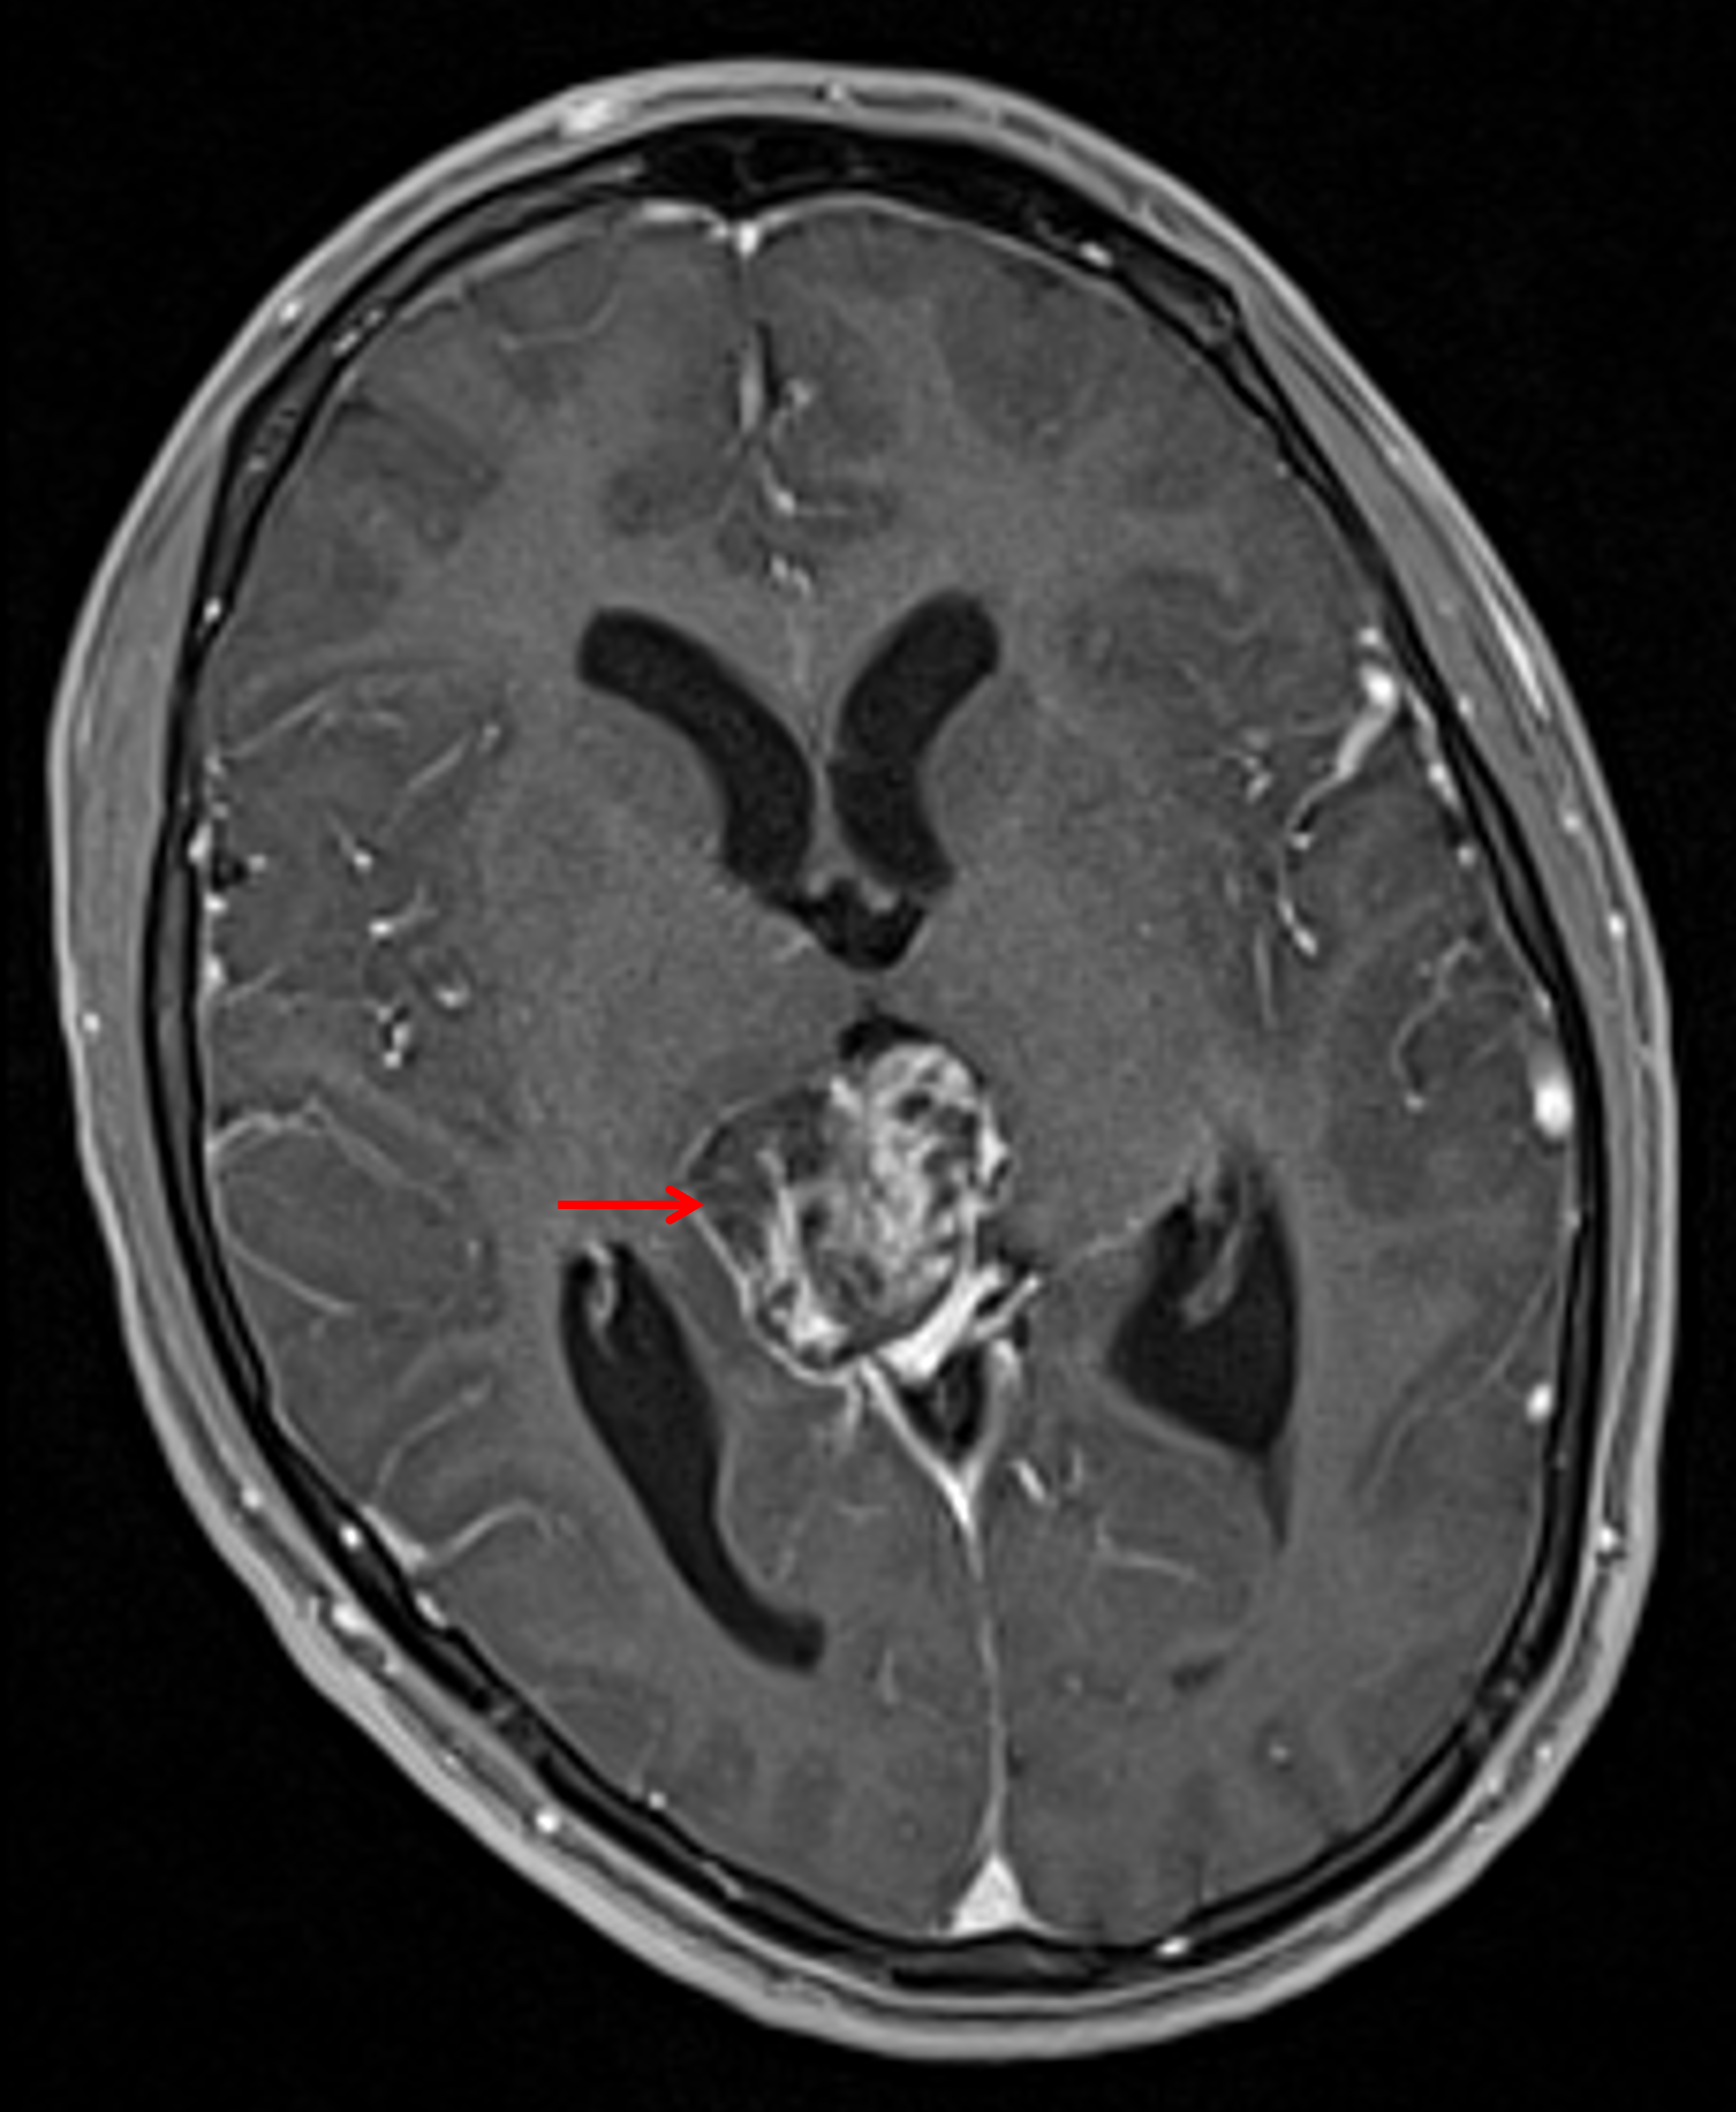

Age: 17

Sex: Male

Indication: Diplopia

MRI

Teratoma (pineal region)